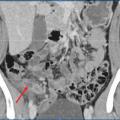

Scanner abdominopelvien injecté : la référence

Le scanner abdominopelvien avec injection intraveineuse de produit de contraste est l’examen de référence, avec une excellente performance diagnostique. Il permet, dans le même temps, d’éliminer de nombreux diag­nostics différentiels et détermine la présence ou non d’une complication de l’appendicite, telle qu’un abcès ou une péritonite. Le diagnostic ­positif repose sur une augmentation du diamètre de l’appendice, une infiltration de la graisse périappendiculaire, un épaississement et une prise de contraste de ses parois (fig. 2).